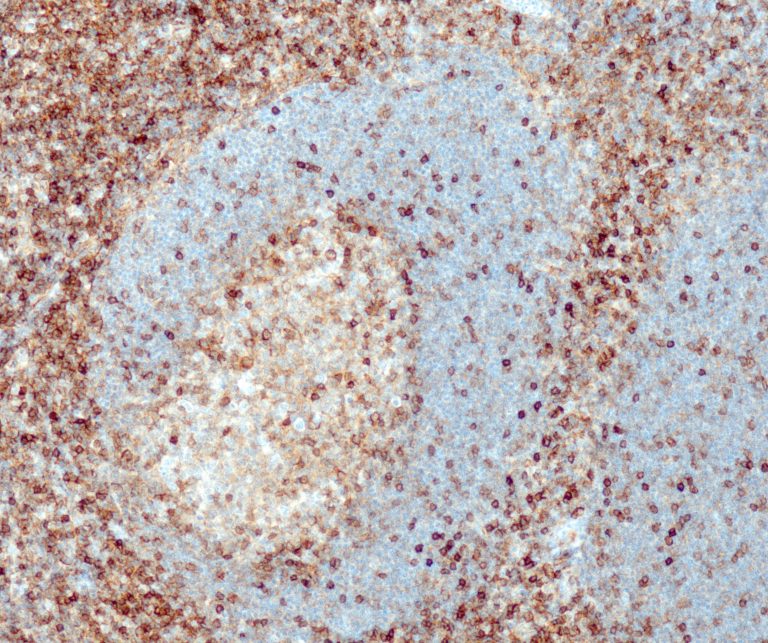

Hematopathology